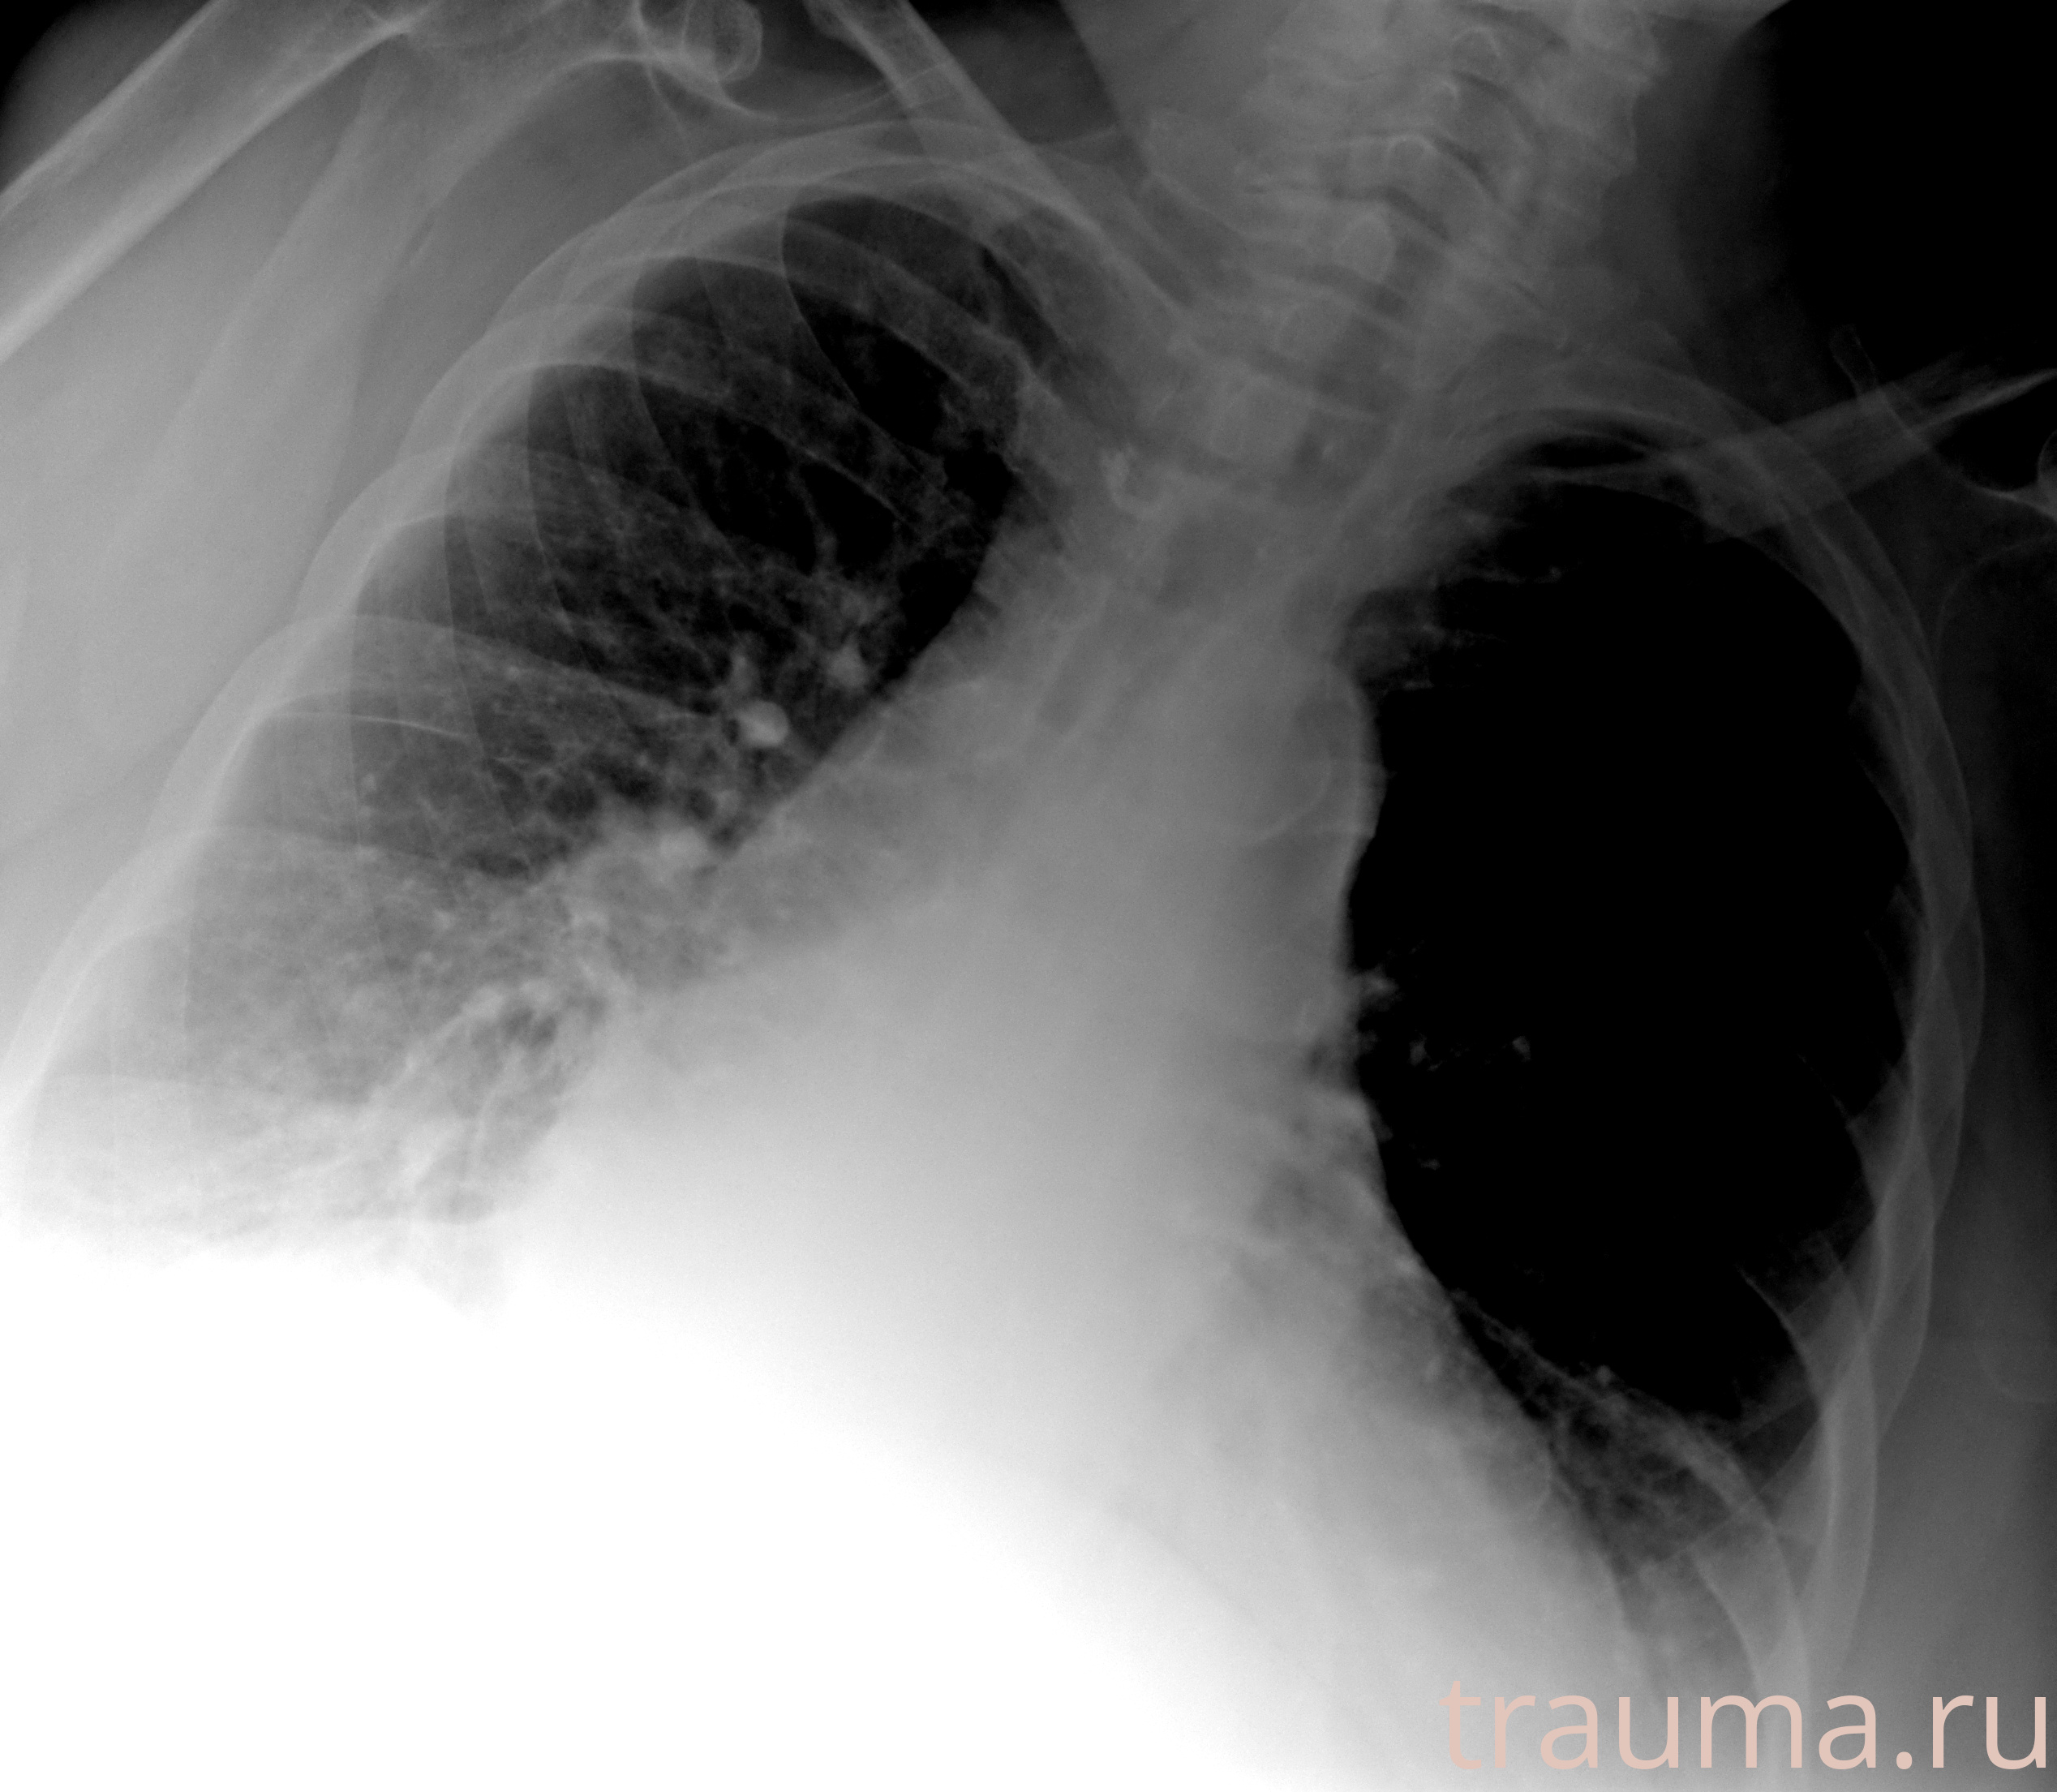

Рентгенограммы

Рентген на дому: по вашему адресу приезжает врач-рентгенолог, травматолог-ортопед с мобильным рентгеновским аппаратом, проводит диагностику травмы или заболевания, делает необходимые рентгенограммы, дает рекомендации по дальнейшему лечению. Получить качественные снимки в домашних условиях возможно благодаря уникальной методике, разработанной МосРентген Центром для института  Склифосовского

при переломе шейки бедра и пневмонии от компании МосРентген Центр - партнера Института имени Склифосовского